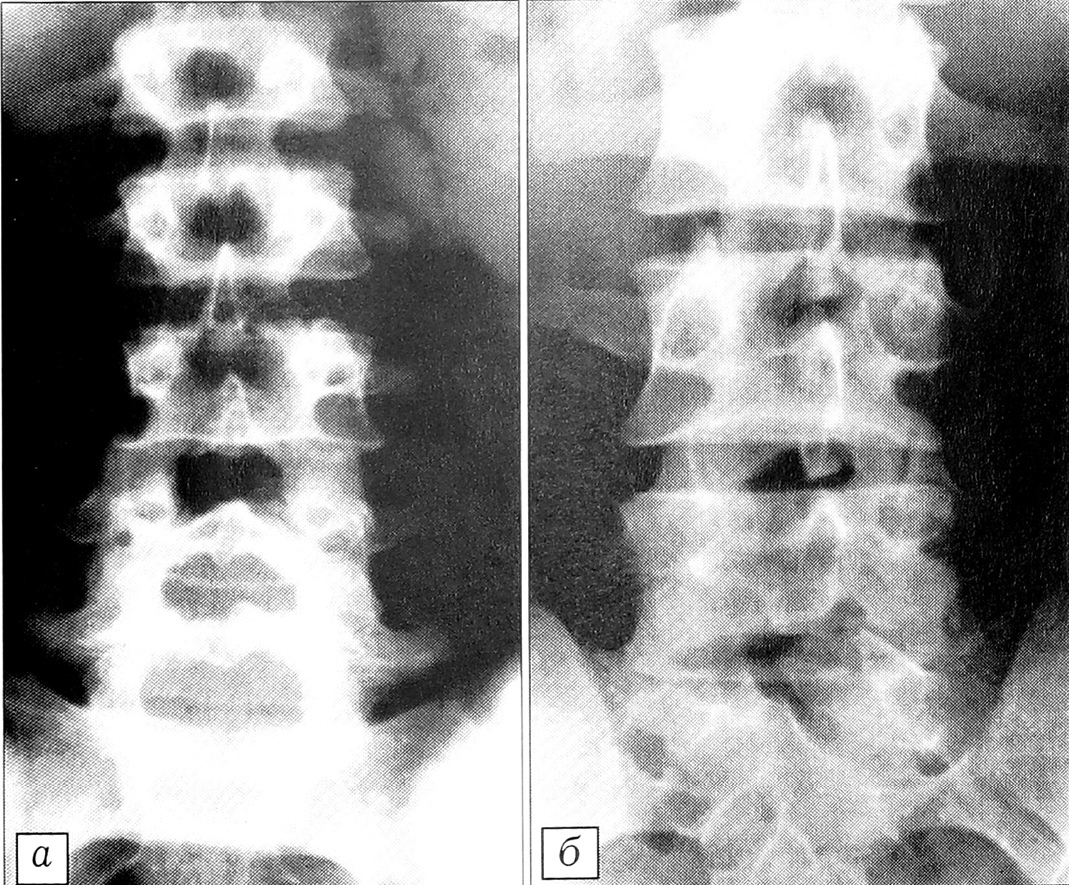

Рис. 4. Эпидурограммы (а — прямая, б, в — боковые) больного 3. 28 лет. Диспластический стеноз позвоночного канала: снижение плотности контрастной тени в участке стеноза позвоночного канала; относительное увеличение плотности контрастной тени проксимальнее и дистальнее участка стеноза; увеличение протяженности контрастированного участка позвоночного канала вплоть до грудного отдела при введении стандартного объема контрастного вещества.

Рис. 6. Эпидурограммы (а — прямая, б — боковая) больного С. 51 года. Исход остеохондропатии позвоночника: фиброз поясничных дисков, диффузный остеопороз, гиперпластический дегенеративный стеноз позвоночного канала — увеличение протяженности контрастированного участка канала при введении стандартного объема контрастного вещества; пятнистость и неровность краев и снижение плотности контрастной тени в центральном отделе позвоночного канала; отсутствие контрастирования латеральных углублений и фораминальных участков; уменьшение заднего эпидурального пространства (за счет гиперплазии дуг и суставных отростков).